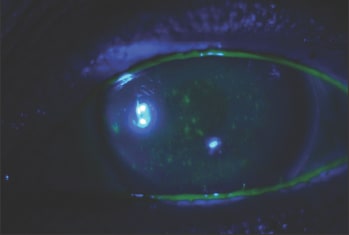

Our first indication that a patient may have dry eye is if he complains of irritation symptoms; eyes that are blurred or fatigued at the end of the day, or irritated after working. A doctor may identify corneal problems, such as a superficial epithelial disease, which could indicate that the patient has dry eye. After identification, always measure the quality and quantity of a patient's tears. I measure the tear breakup time and check if the patient has dye staining on the surface of their eye. We use lissamine green for the conjunctiva and fluorescein, which stains the cornea. These tests offer a simple means of identifying ocular surface changes, and they help to gauge the severity and type of dry eye. We can then tailor the treatment to the specific problem.

Figure 1. Exposure zone bulbar conjunctival staining in a patient with combined aqueous tear deficiency and MGD.

Figure 2. Severe diffuse corneal fluorescein staining in a patient with Sjögren's syndrome aqueous tear deficiency.